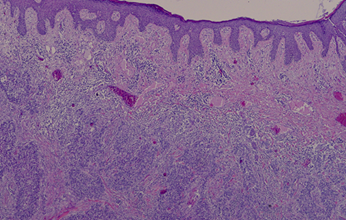

Se intervino en mayo del 2021 realizando exéresis del implante de 4x2,5 cm con márgenes libres. La anatomía patológica confirmó el hecho de ser una metástasis (fig.1) y no un primario ya que no había afectación de epidermis (fig.2, fig.3), el tumor crecía desde las capas inferiores a las superiores.

Fig.3.  Imagen histológica.